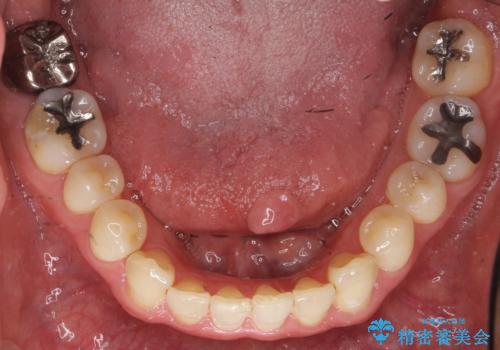

精査したところ、右下の一番奥の歯(右下7)に歯肉縁下に及ぶ深いう蝕を認めました。

神経がない歯であり痛みが出ないことから、自覚症状がほとんどなくう蝕が大きく進行してしまったと考えられます。

銀歯を除去し、歯周外科処置(右下7遠心の骨整形及びディスタルウェッジ)を行った後にメタルボンドクラウンによる補綴を行いました。

隣の歯(右下6)はセラミックインレーで修復しました。